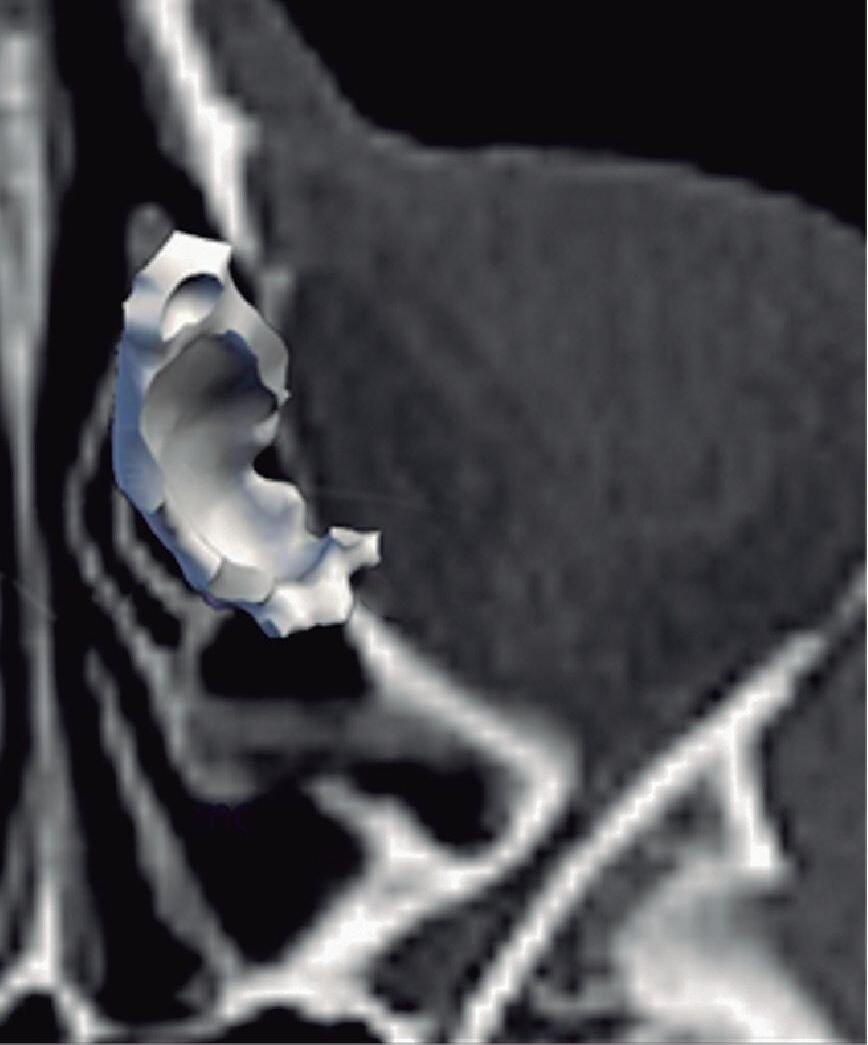

1-4. TC e reconstrução 3D com destaque para estrutura etmoidal (em vermelho), funcionando como câmaras de baixa pressão para drenagem do seio maxilar.

1-7. TC com reconstrução 3D mostrando em vermelho apenas o seio etmoidal e não o osso etmoidal, e sua relação com a fossa nasal, o seio maxilar, órbita e fossa anterior.